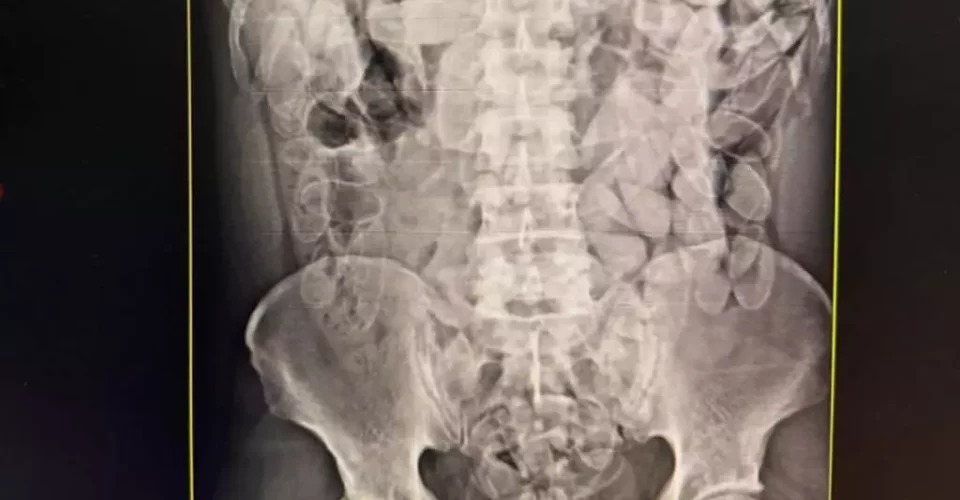

Os três foram conduzidos à Santa Casa de Corumbá, onde exames de raio-X confirmaram as suspeitas: cada um deles havia ingerido cerca de 100 cápsulas de pasta base de cocaína. No total, os agentes contabilizaram aproximadamente 3,5 quilos da droga escondida nos corpos dos suspeitos.